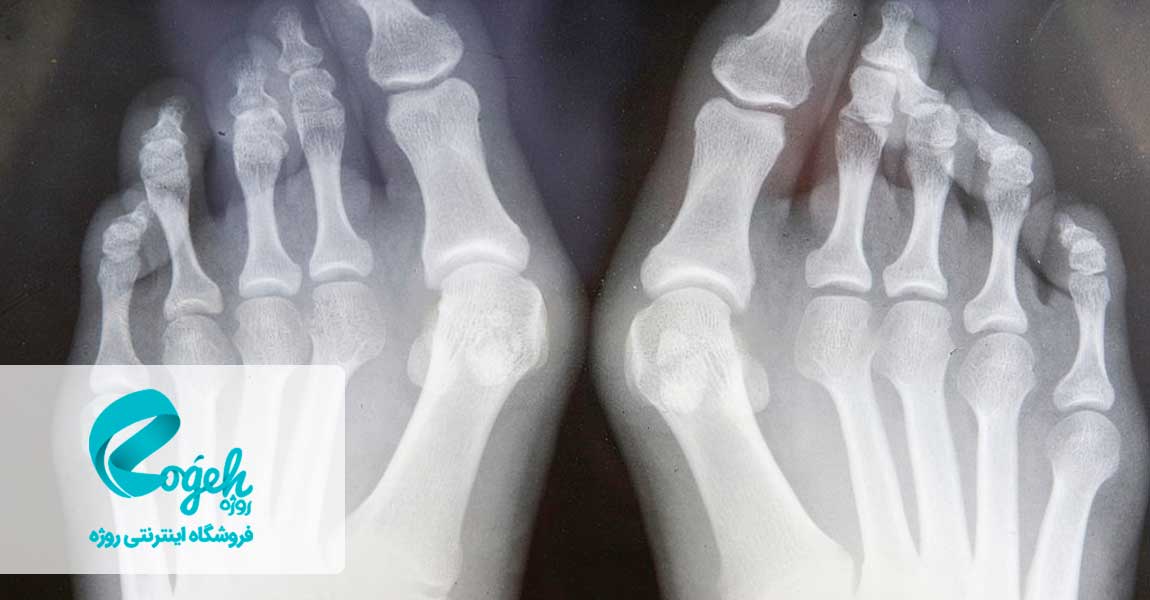

درمان انحراف شست پا معضل بسیاری از مردم است. چرا که بیرون زدگی استخوان انگشت، علاوه بر ظاهر ناخوشایندی که دارد، وقتی که کفش میپوشید خیلی آزاردهنده است. بونیون (bunion) تودهای استخوانی است که در مفصل واقع در قاعدهی شست پا ایجاد میشود. این توده زمانی به وجود میآید که شست پا به سمت انگشت مجاورش فشار دادهشود و مفصل شست برجسته و بزرگ شود. این عارضه، گاهی با علائمی همراه است. گاهاً هم بدون علائم خواهد بود.

انحراف شست پا یک برآمدگی استخوانی در مفصل پایهی انگشت بزرگ است. انحراف شست پا زمانی ایجاد میشود که انگشت بزرگ پا به انگشت کناری فشار وارد کرده و باعث بزرگ شدگی و بیرون زدگی مفصل شست پا شود. در این حالت پوست انگشت دارای انحراف، قرمزی و تورم خواهد شد. پوشیدن کفشهای تنگ و باریک باعث ایجاد انحراف و یا تشدید انحراف موجود در شست پا میشود. همچنین انحراف شست پا در نتیجهی وجود یک مشکل ساختاری ژنتیکی، فشار به پا یا مشکلاتی همچون آرتریت ایجاد میشود. درمان انحراف شست پا بسیار ضروری است چرا که این بیماری رفته رفته شدیدتر میشود.

به دلیل متفاوت بودن موارد انحراف انگشت شست پا ازنظر شکل و اندازه، روشهای جراحی استفادهشده برای ترمیم آنها نیز متفاوت خواهند بود. در بیشتر موارد، عمل جراحی انحراف انگشت شست پا عبارت است از اصلاح موقعیت استخوان شست و ترمیم بافتهای نرم اطراف آن.